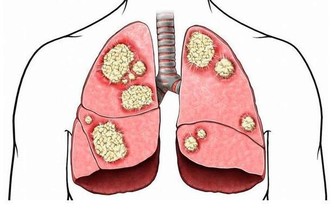

5、損害腎臟。

尿酸長期高,會導致肌酐高,這意味著腎臟可能出現問題,比如腎功能不全、甚至腎衰竭、尿毒症。尿酸結晶沉積導致腎小動脈和慢性間質炎症使腎損害加重。有研究顯示,尿酸可直接使腎小球入球小動脈發生微血管病變,導致慢性腎臟疾病。

高尿酸會增加腎功能降低風險21%,增加因慢性腎病死亡風險68%。